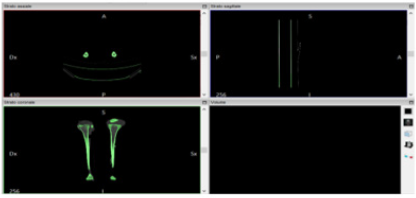

Following the import, the software allows to visualize the biological structure of interest in the three main axes of the human body (Figure 8)[10]. The next step is to segment the image using a colored mask. The mask is nothing but gray threshold level comparable to a certain tissue density. By setting the density range, the software highlights a specific region and creates its three-dimensional model, eliminating the rest. There is the possibility of pre-defined range (for example: compact bone, spongy bone, skin, muscular tissue etc.) or it can be changed manually. After the correct identification of the mask, the 3D surface is generated using the proper command (Figure 9). In the analyzed case it was preferred to use the “ Compact bone (adult) “ because the range was more limited avoiding other possible tissue inclusion. When the mask covers the right areas, the creation of the three-dimensional surface is performed. This is displayed in the lower right window (Figure 10). Once the 3D surface is created and exported in STL format for further modifications. Generally, the mesh created by In Vesalius is coarse and not homogeneous, so it needs an optimization process.